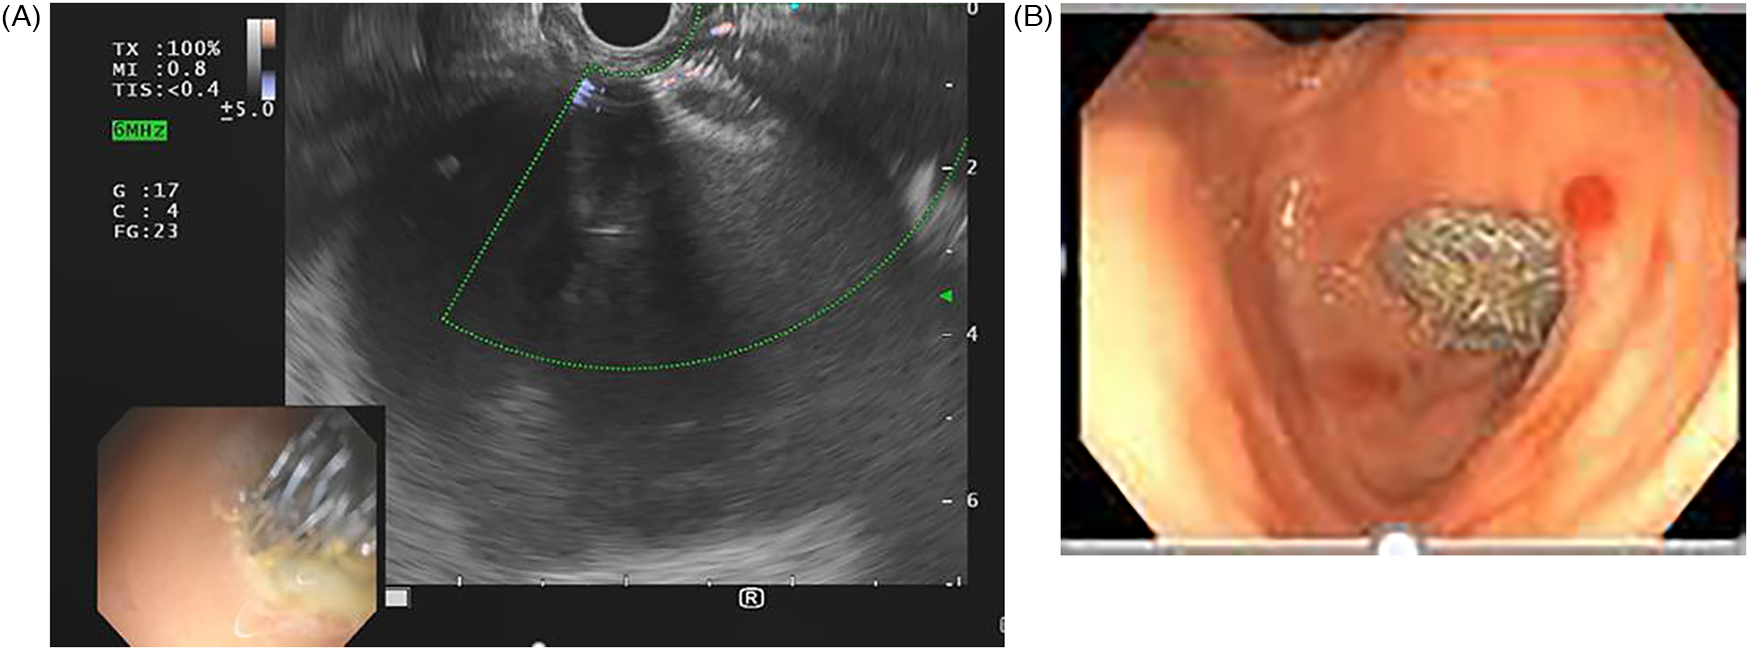

Three EUS procedures with lumen-apposing metal stents (LAMS) were performed to manage acute necrotizing pancreatitis with pseudocyst formation (Figures 4, 5A,B) following EUS-guided drainage of pseudocysts, avoiding the need for surgical interventions. Pancreatic necrosectomy was performed using a standard esophagogastroduodenoscopy (EGD), navigating through the AXIOS™ stent (Boston Scientific, Marlborough, Mass, USA) and using biopsy/rat-tooth forceps for the removal of any necrotic pancreatic tissue. Technical success was achieved in 100% procedure.

Figure 4. Computed tomography (CT) abdomen demonstrating a pancreatic pseudocyst (indicated by the yellow arrow).

Figure 5. (A) Linear EUS during placement of lumen-apposing metal stent (LAMS). (B) Endosopic view post-LAMS placement.